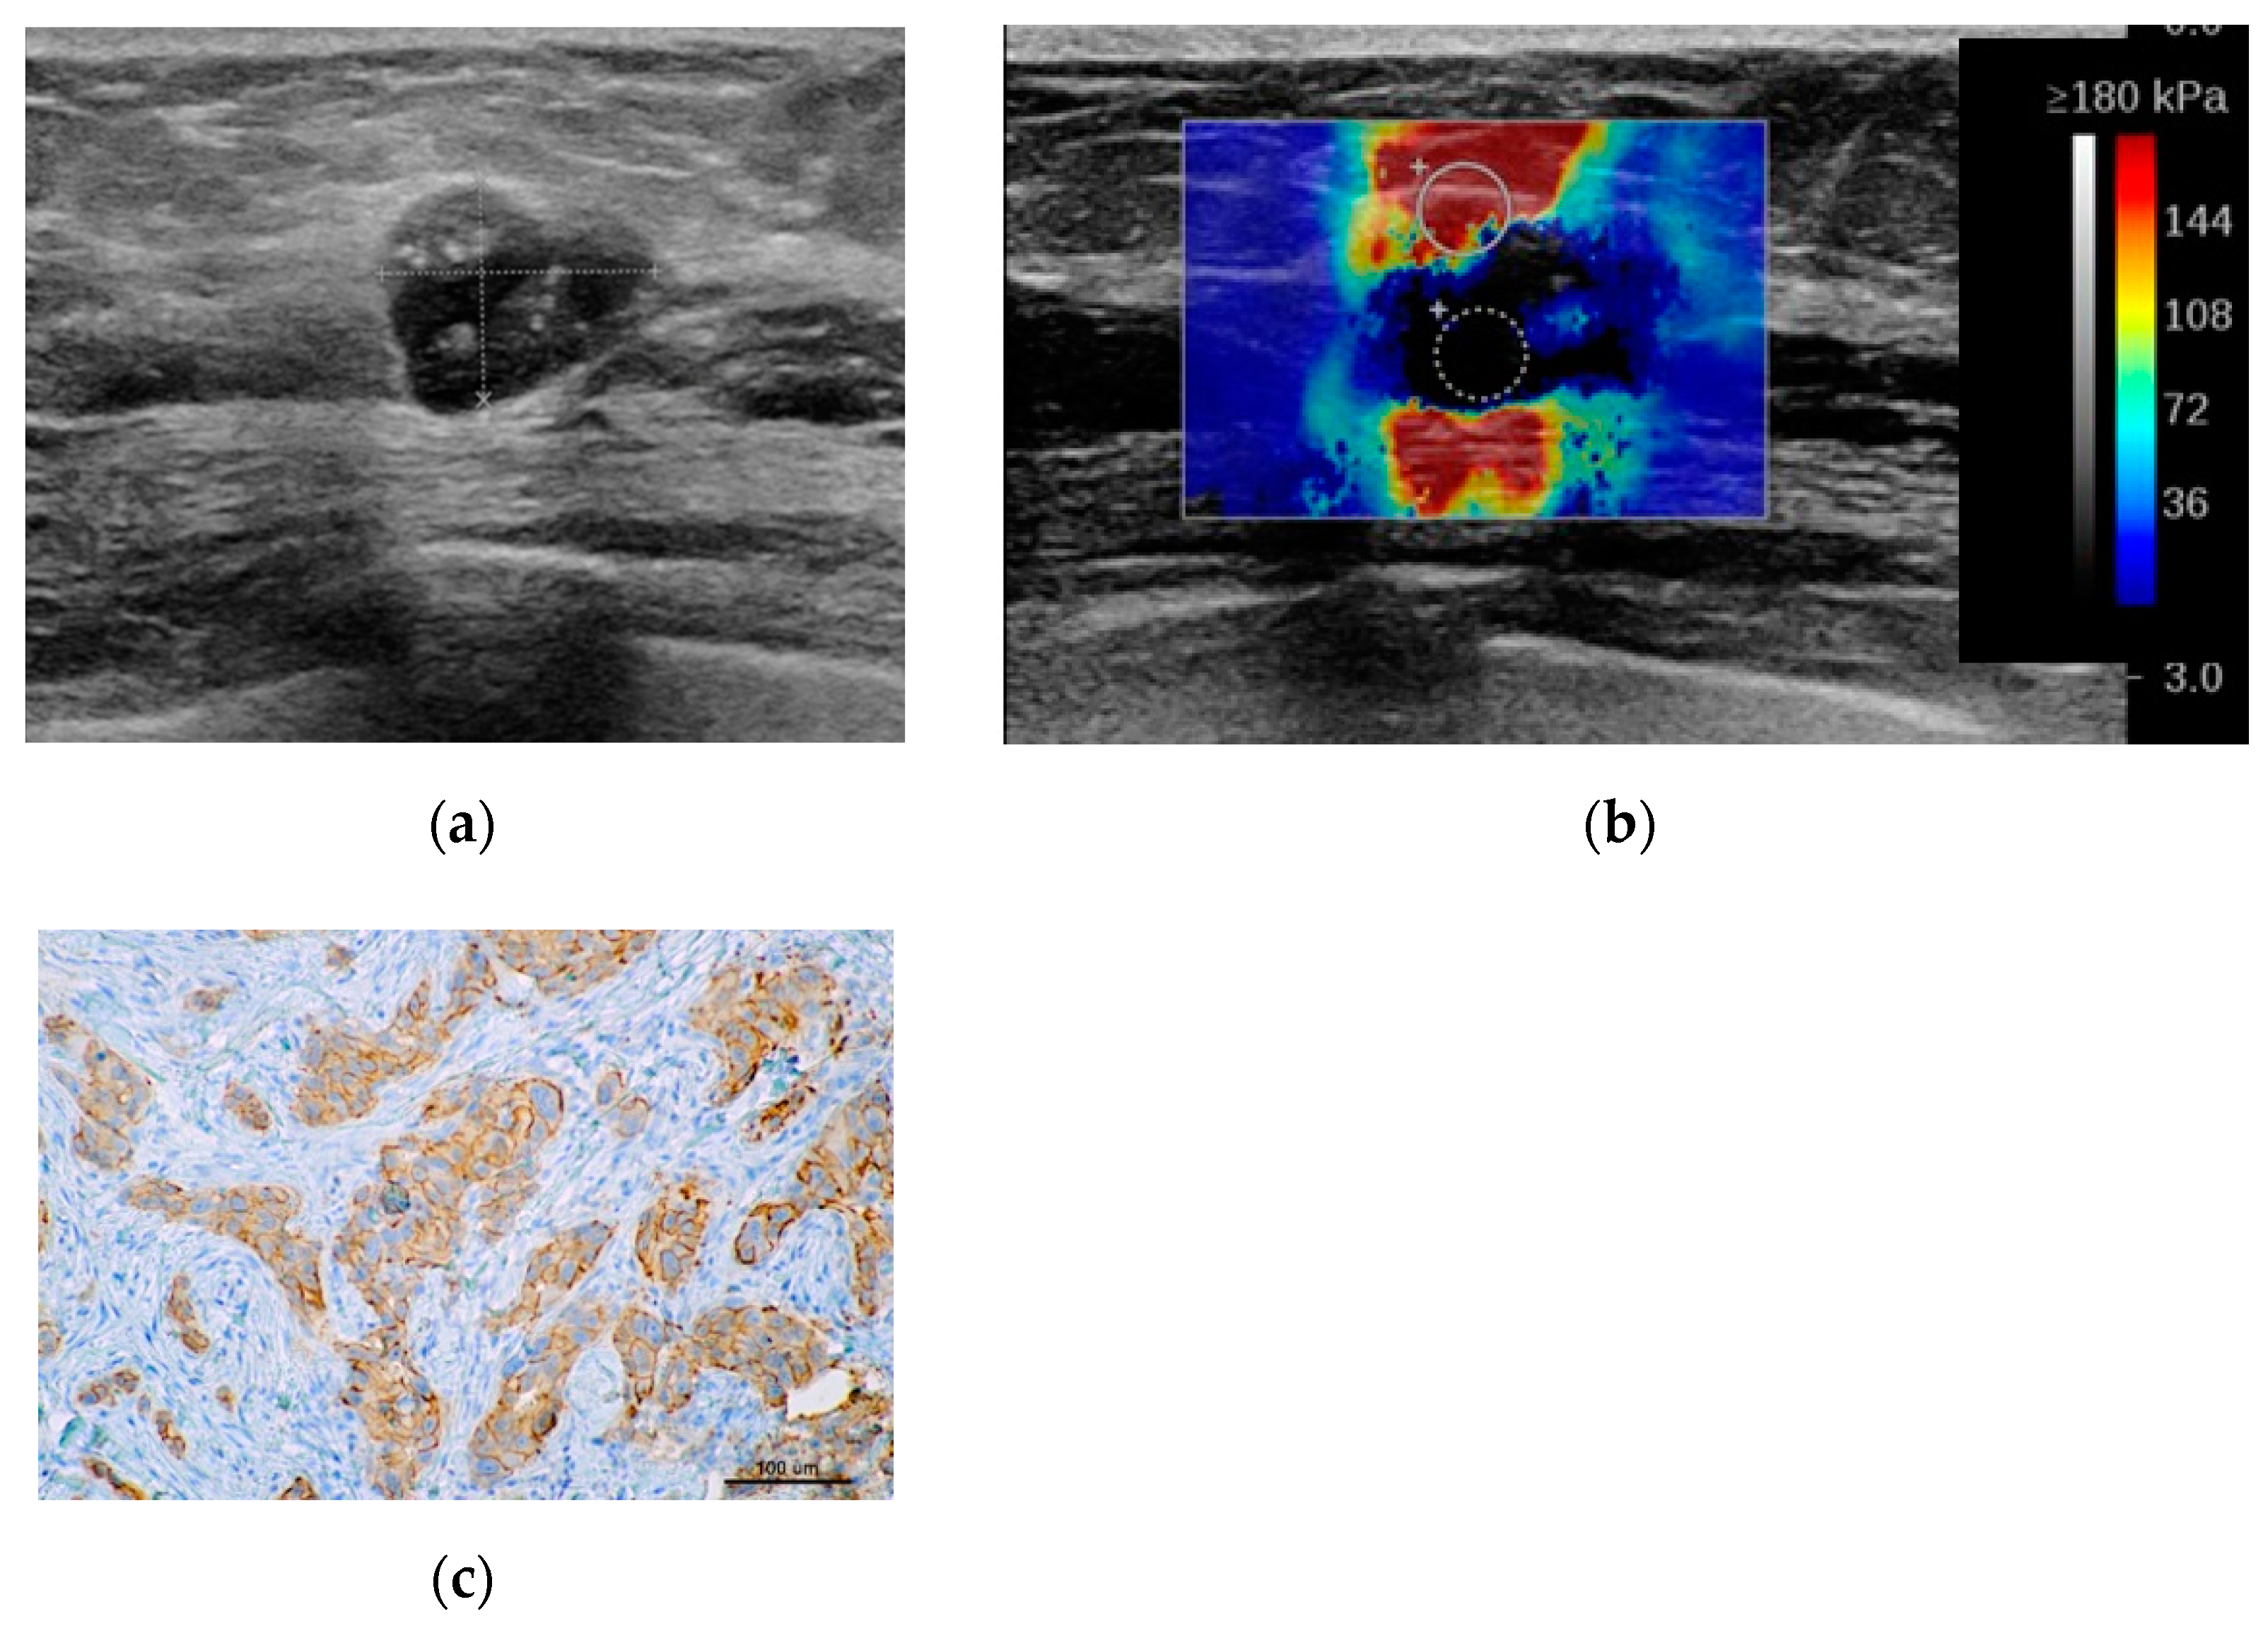

2.2. Sonoelastography

- Soft (incorporate: Tsukuba1,Tsukuba2, E max < 80 kPa)

- Intermediate (incorporate: Tsukuba3, E max > 80 kPa < 160 kPa)

- Hard (incorporate: Tsukuba 4,Tsukuba5, E max > 160 kPa)